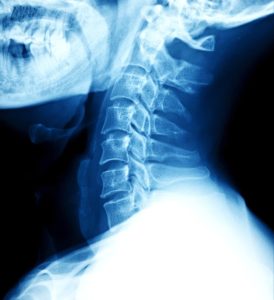

Common types of neck injuries

Work-related neck injuries vary in severity. Some of the most common work-related neck injuries include: